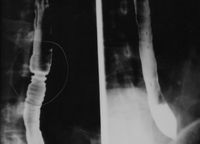

상부위장관조영술은 X선을 이용하여 식도, 위, 십이지장 등 상부 위장관의 외형과 기능을 검사하는 방법으로, 바륨 조영제를 사용하여 식도 역류, 궤양, 종양, 위장관 운동 이상 등을 진단하며, 바륨 삼킴 검사, 바륨 식사 검사 등 다양한 종류가 있다. - 바륨 - 바륨 동위 원소

황산 바륨은 1908년에 소화기계의 의료 영상(X선 영상)에서 조영제로 처음 사용되었다.[14]

황산바륨은 독성이 낮고 약 4.5 g/cm3의 비교적 높은 밀도(따라서 X선에 대한 불투명도)를 가지고 있다. 이러한 이유로 소화기계의 X선 영상에서 조영제로 사용된다("바륨 밀" 및 "바륨 관장").[2] 리토폰은 황화물에 노출되어도 어두워지지 않는 우수한 피복력을 가진 영구 백색 안료이다.[20]